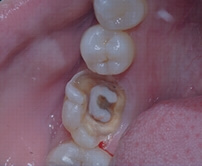

Deep Cavity

Pulp Inflammation